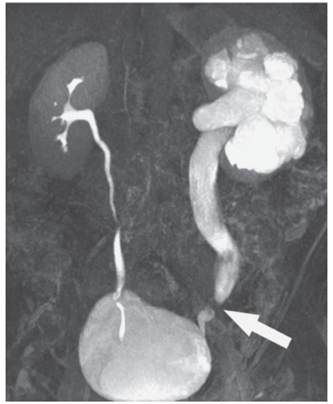

Observe a imagem a seguir.

Nessa RM coronal ponderada em T1, obtida 5 minutos após administração por via intravenosa de gadolínio, é correto afirmar que